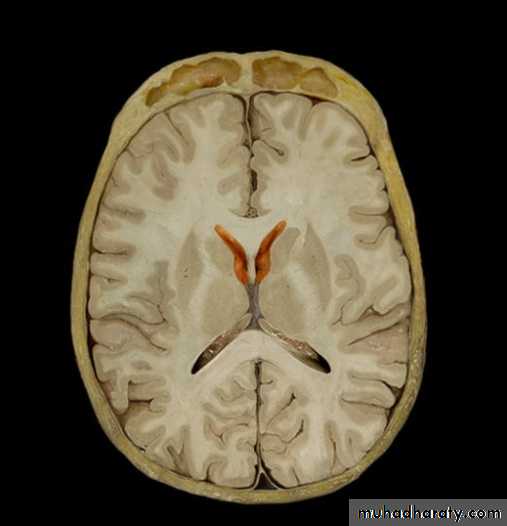

The lateral ventricles

• Situated in the cerebral hemispheres, it has a• body, an anterior horn in the frontal pole, posterior

• horn in the occipital pole & inferior horn in the

• temporal pole.

• The two lateral ventricles are interconnected by

• interventricular foramen and it also communicates

• with the 3rd ventricle.

• All ventricles are lined by ependyma.

3rd Ventricle

• It lies below the lateral ventricles.

• It is a cavity of the diencephalon. In the roof there is

choroid plexus, that produce CSF.

• Superiorly it communicates with the two lateral

ventricles through the interventricular foramen.

• Inferiorly it communicates with the 4th ventricle

through the cerebral aqueduct.

• The lateral wall is formed by thalamus and

• hypothalamus.

Ventricles

Lateral

Third

Fourth